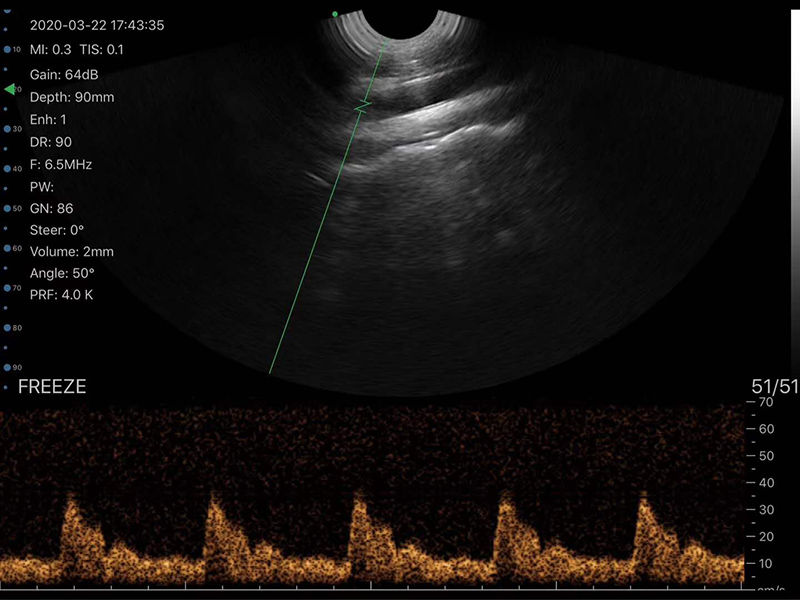

Scanning Mode: Electronic R13 Convex Array, ensuring stable and clear scanning for animal diagnosis

Image Mode: B, B/M, Color, PW, PDI – multiple modes to meet different clinical detection needs

Working Frequency: 6/8MHz, adjustable to adapt to different animal body parts and detection requirements

Scan Angle: 149°, wide scanning range for comprehensive observation of target areas

Scan Depth: 30-120mm, flexible adjustment to fit small and large animals

Dynamic Range: 40/50/60/70/80/90/100/110 – flexible adjustment to enhance image detail and contrast